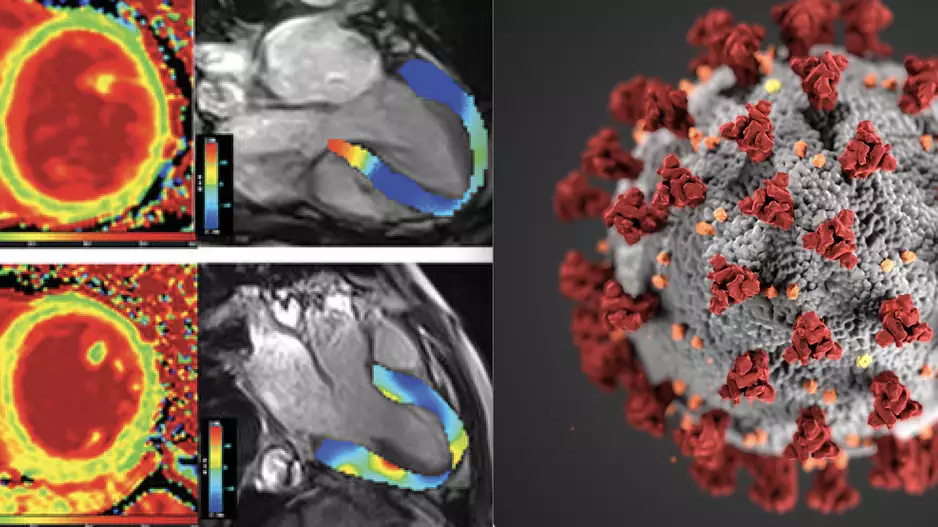

The American College of Cardiology (ACC) has issued a new expert consensus decision pathway for the evaluation and management of adults with cardiovascular consequences stemming from a…

The University of California San Diego Health has debuted a new technology that may offer a better way to assess and treat…